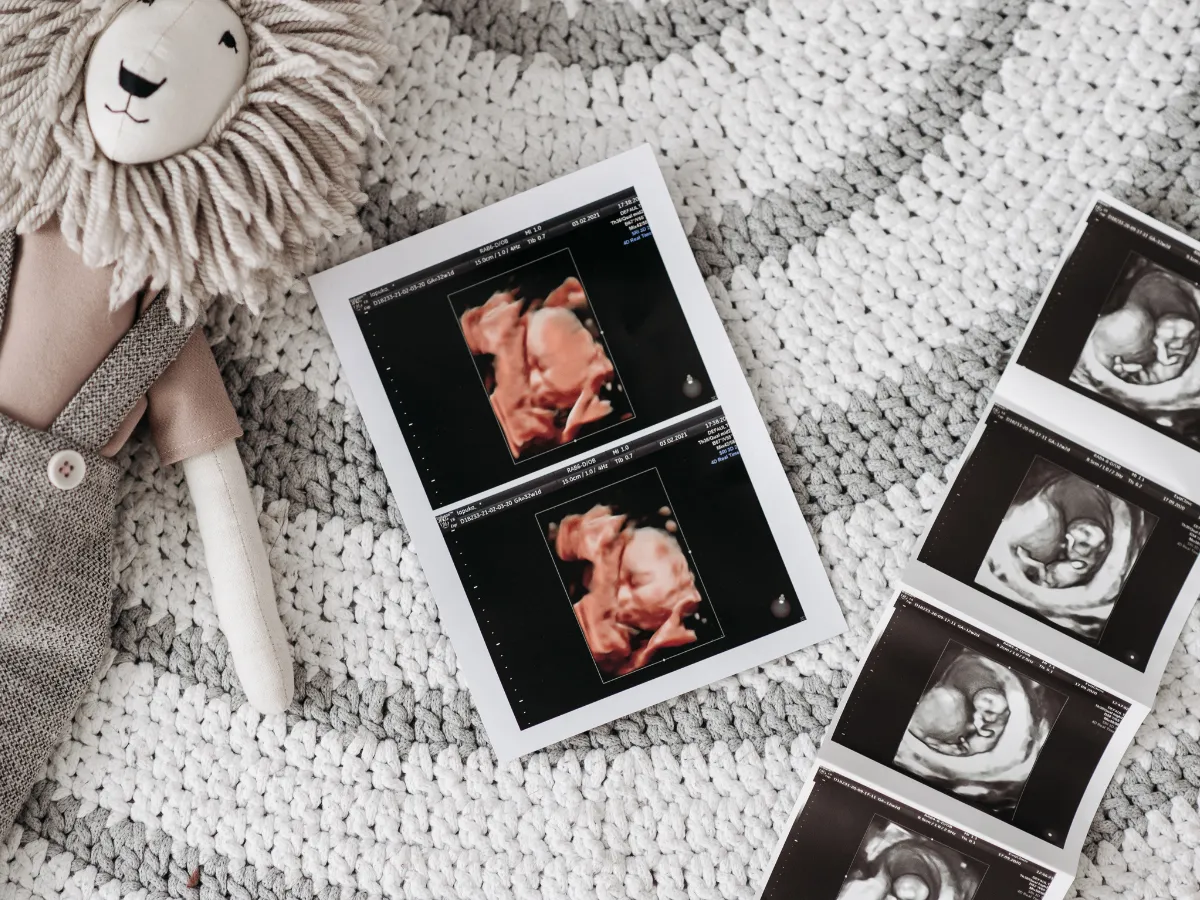

4Dエコー

お腹の赤ちゃんに会える時間

お腹の中の赤ちゃんの表情や動きを、立体的な映像でリアルタイムに確認できます。ご家族と一緒に見ることで、妊娠中の大切な思い出にも。健診とは別に記念目的でもご利用いただけます。